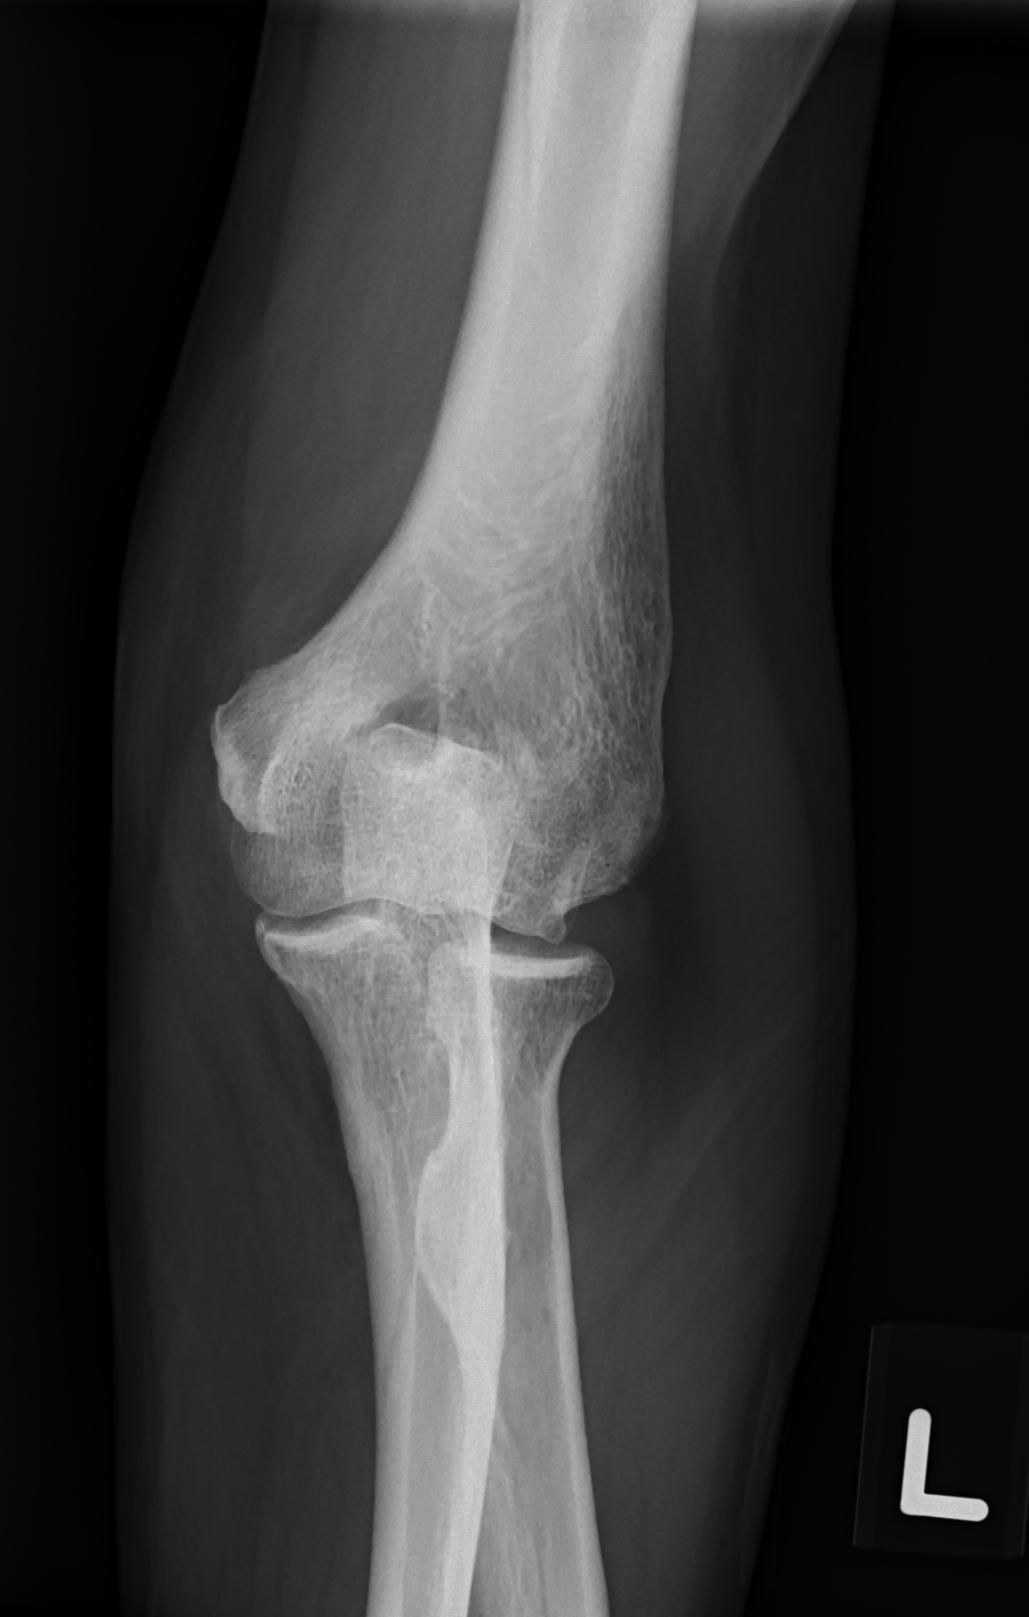

| Patient: TAY LIANG KWANG (M) | Birth date: 10/31/1949 | ID: S0185622G |

| Study | ID | Date | Accession # | Thumbnails | Report | XR ELBOW, AP & LAT, LEFT | 2766356 | 08/21/2019 | 2766356 | ... | MR WHOLE SPINE (FULL STUDY) | 32376 | 08/23/2019 | 2766095 | ... | XR CERVICAL SPINE, AP & LATERAL | 2765876 | 08/20/2019 | 2765876 |